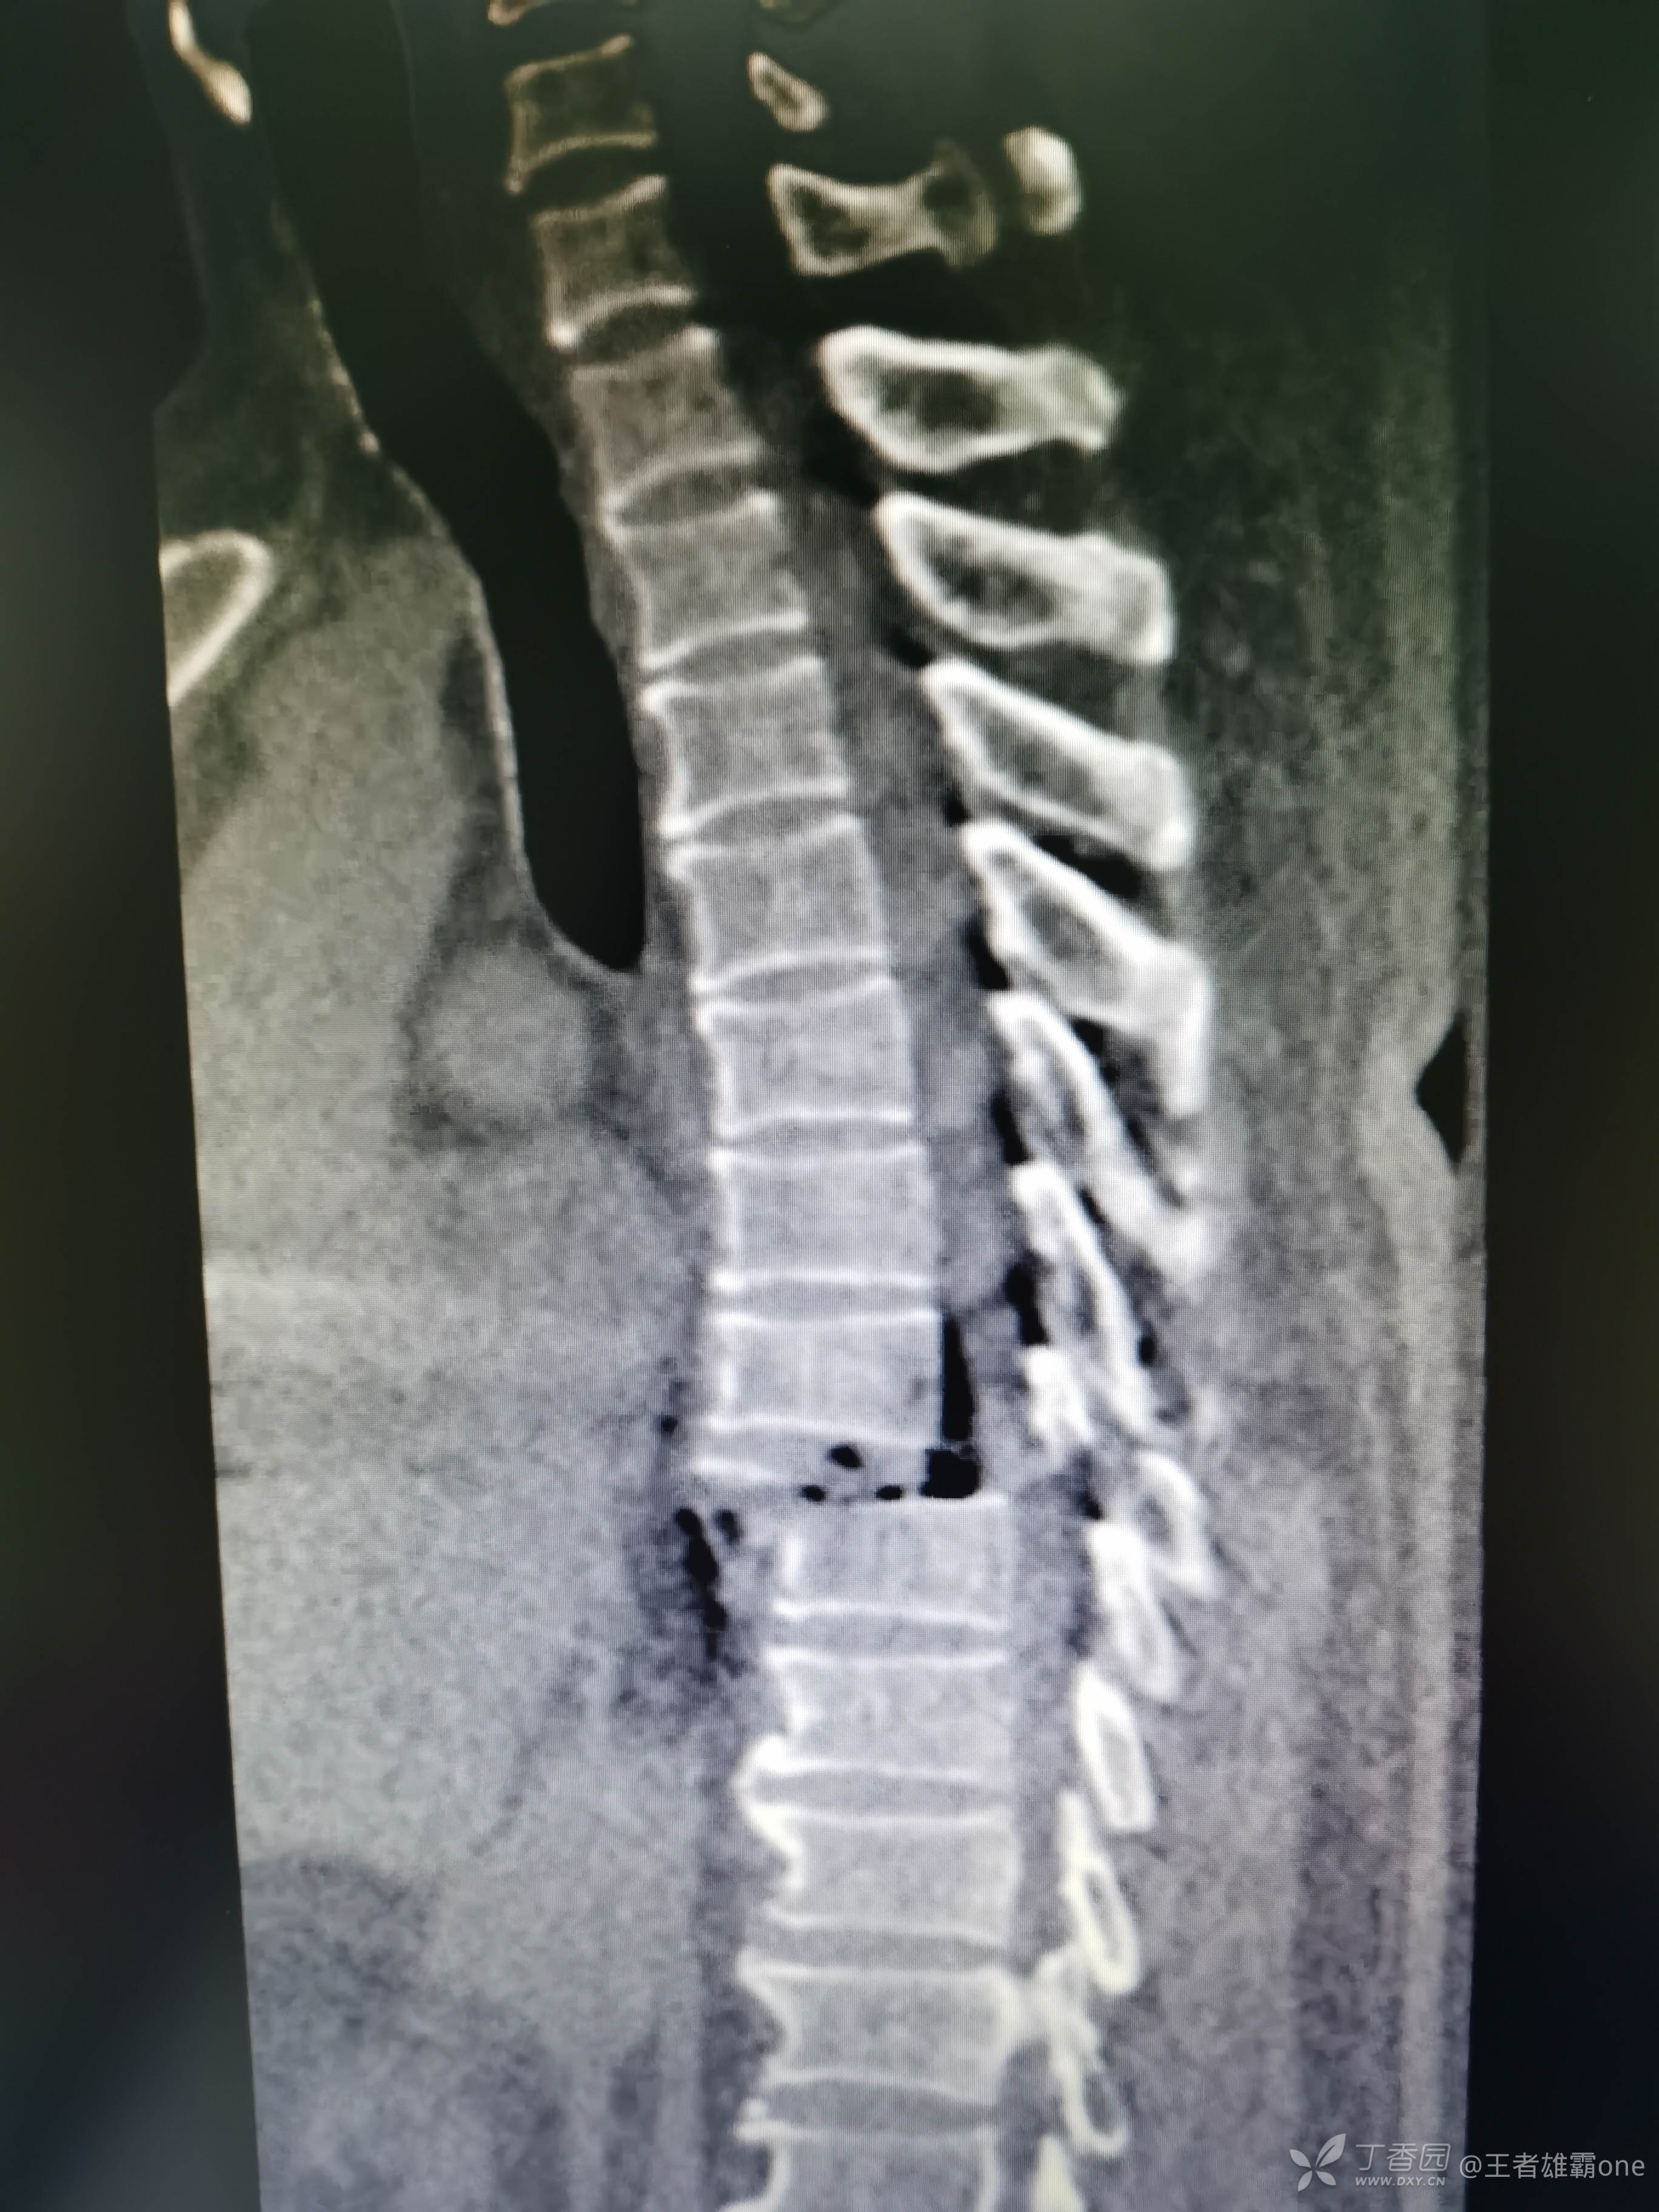

查胸椎CT: